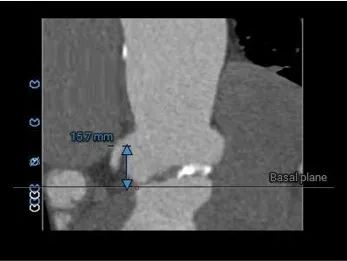

左冠15.7,右冠19.4,综合分析冠脉阻挡风险适中

瓣上多平面分析